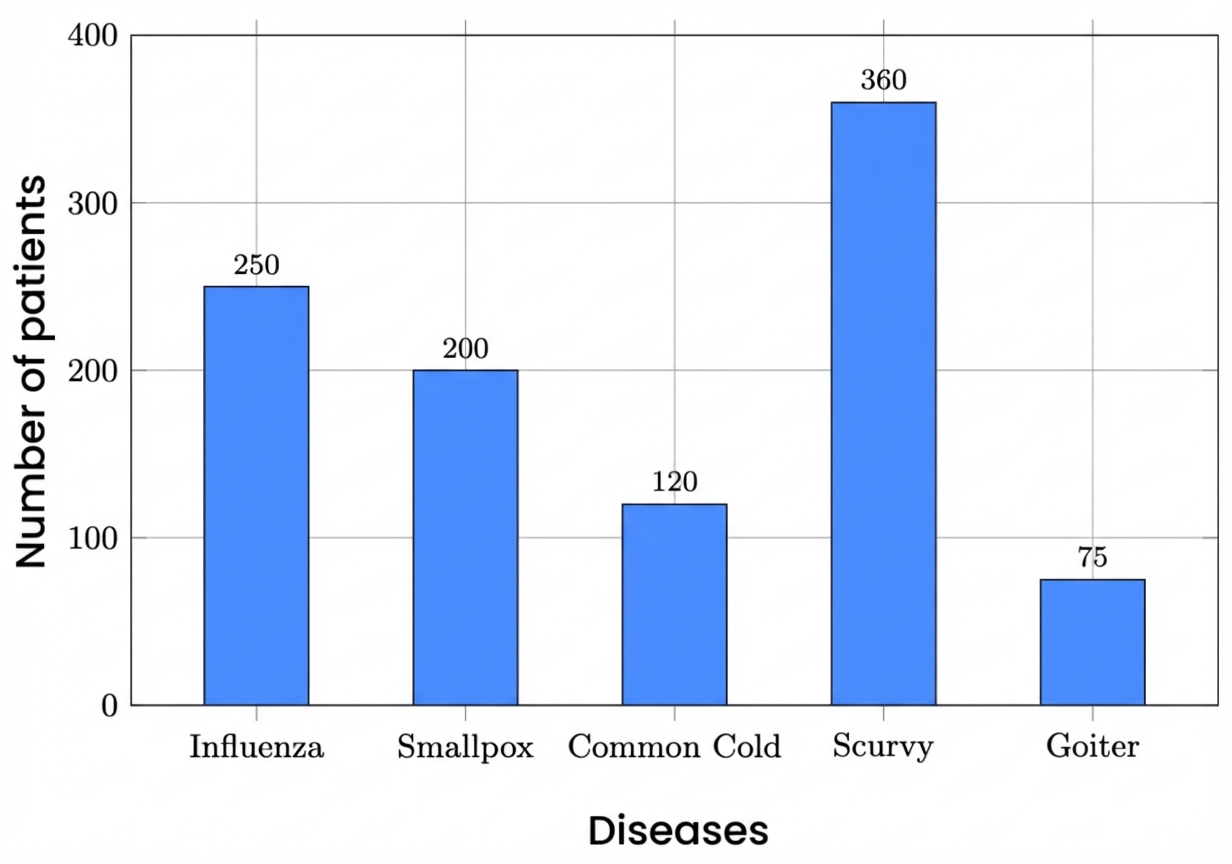

Find the mode in the given bar chart.

|

No changes |

Rationale: The question text and the image contain no Australian-specific spelling, terminology, units, or cultural references. The bar chart uses universal academic grading (A-E) and standard mathematical terminology. |